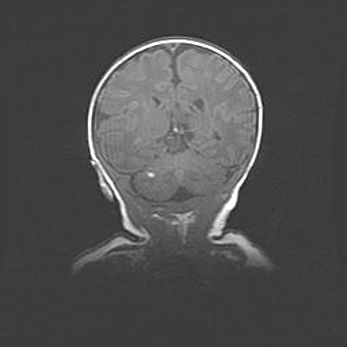

Аномалия Денди-Уокера. Признаки гипоплазии мозолистого тела.

Возраст: 5 месяцев 3 дня

Вес: 5550 г

Пол: мужской

Окружность головы: 39 см

Срок гестации: 40 недель

Аномалия Денди-Уокера – это порок развития головного мозга, для которого характерна триада симптомов: гипотрофия или аплазия червя мозжечка и/или полушарий мозжечка, расширение четвёртого желудочка с формированием ликворной кисты задней черепной ямки, гипертензионная гидроцефалия различной степени.

Гипоплазия мозолистого тела относится к дефектам внутриутробного этапа развития мозговой ткани, возникающим в процессе закладки структур головного мозга, что происходит на начальных этапах развития эмбриона.